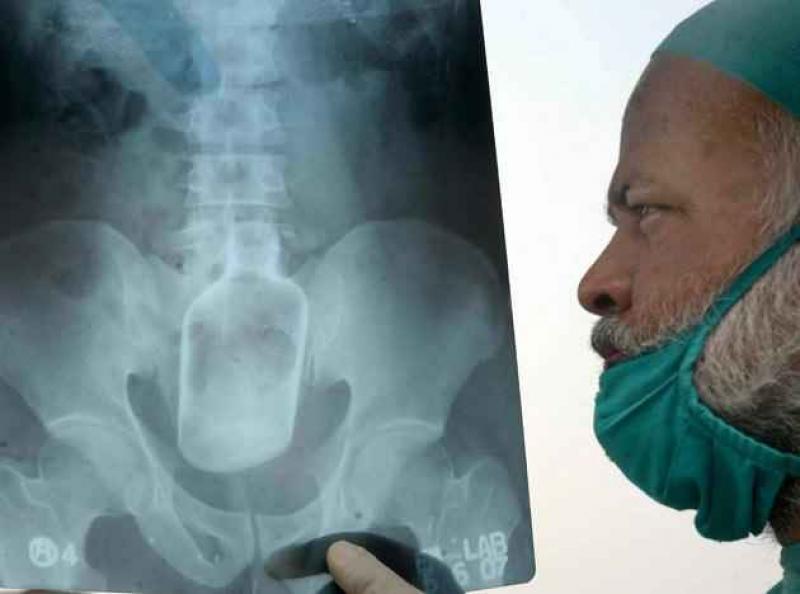

Röntgenfoto's zijn een medische uitvinding die ons al decennia lang helpt. Ze geven een nieuw gezichtspunt als het gaat om het vinden en behandelen van inwendige verwondingen. De machines kunnen opmerkelijke beelden vastleggen van het menselijk lichaam en ze documenteren vaak gruwelijke verwondingen. Een wonde van iemand zien, is al erg, maar als je ook kan zien wat de schade in het lichaam is, dat is nog veel erger. We hebben 12 tegelijk fascinerende, gruwelijke en hilarische röntgenfoto's op een rijtje gezet. Stel jezelf maar eens de vraag hoe iemand ooit aan die verwondingen is gekomen. We beginnen nog rustig.